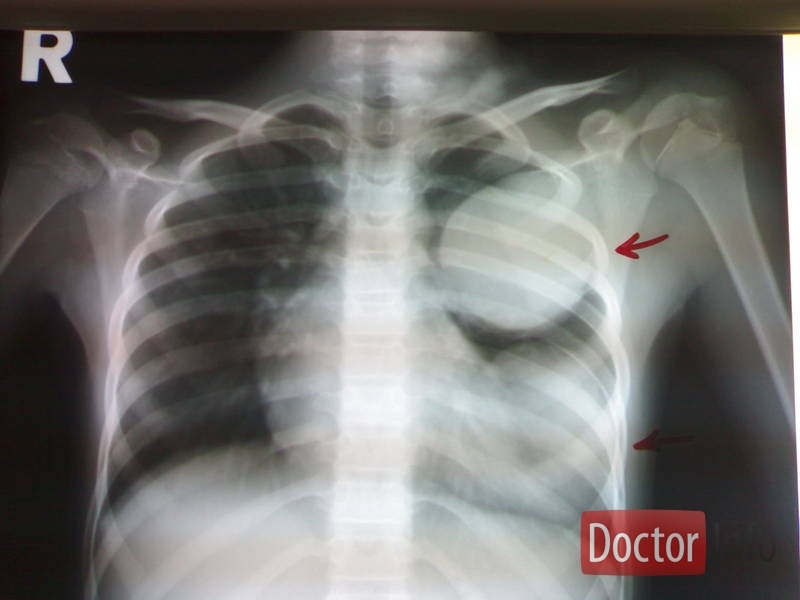

На втором месте стоит эхинококкоз легкого(20-30%)-в нем так же развивается киста.По мере ее роста в тканях легкого,происходит сдавление окружающих тканей,появляется кашель,в начале сухой,позже присоединяется мокрота с кровью,одышка.

Наиболее точным диагностическим методом на данный момент является компьютерная томография и магнитно-ядерно резонансная томография. Они позволяют точно указать на локализацию кисты,толщину ее стенок и размеры.